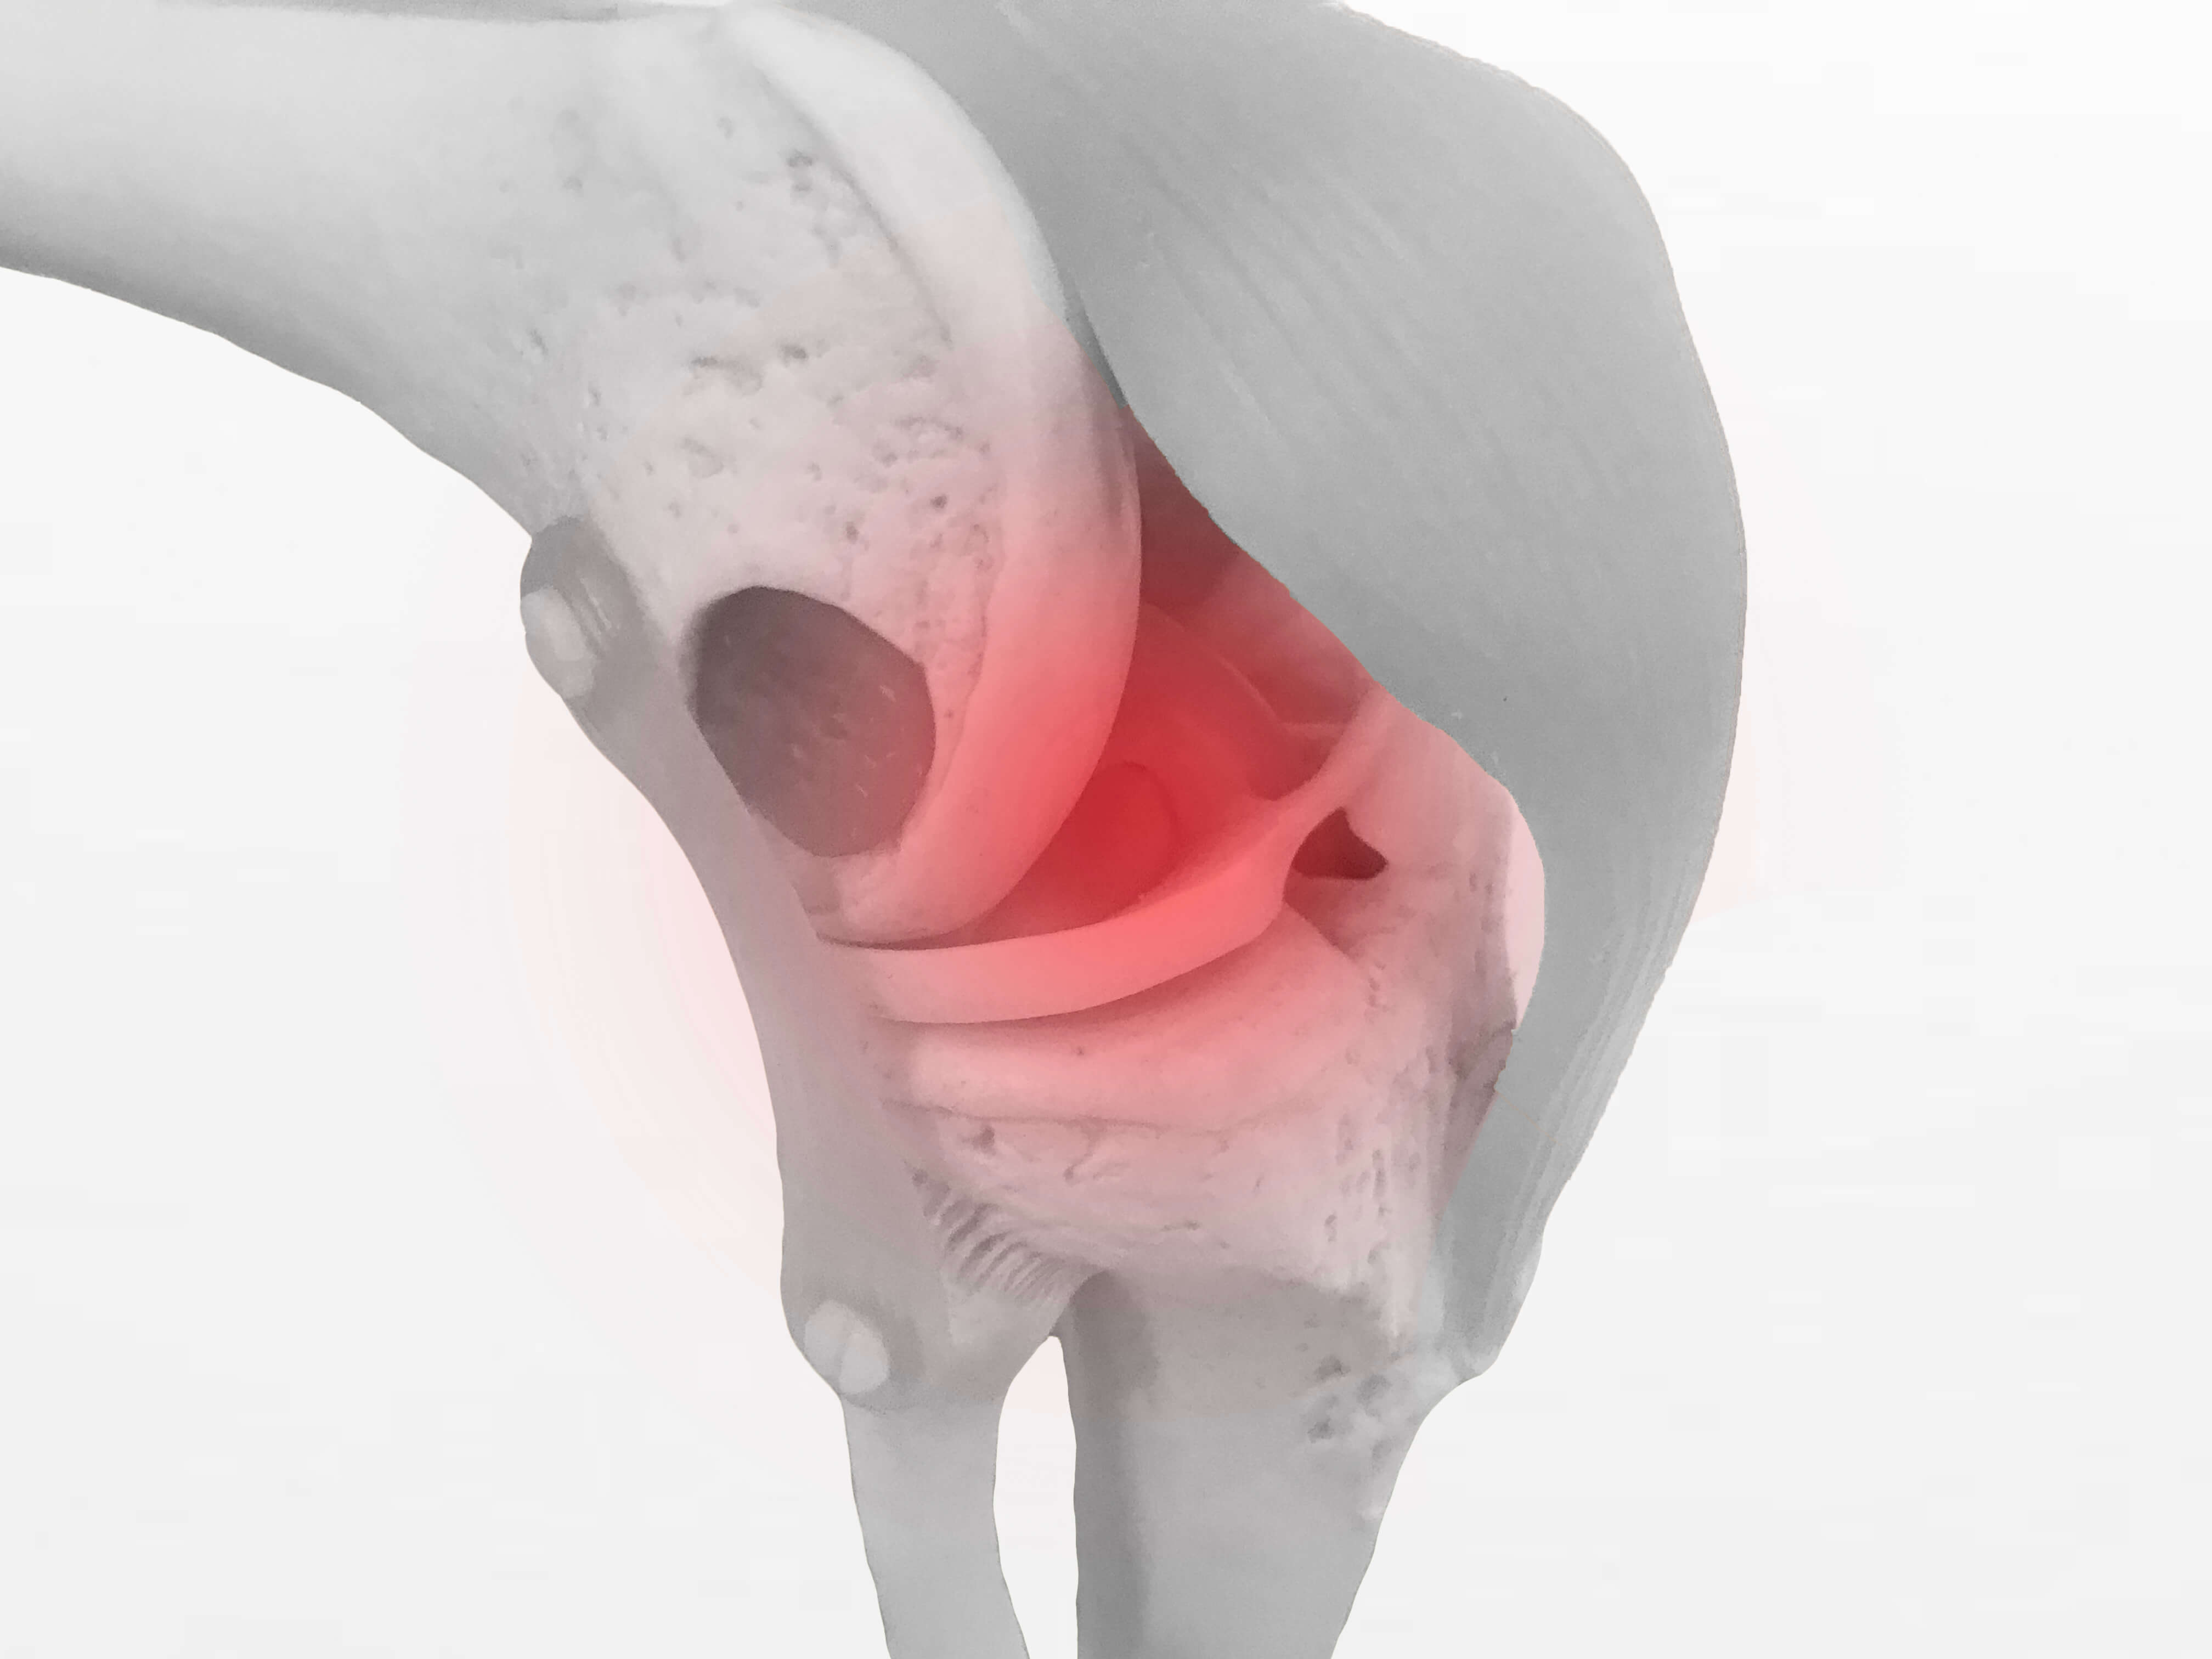

人工膝関節置換術と術後感染症です。

人工膝関節置換術後の術後合併症には色々ありますが

そのなかのひとつに術後感染症があります。

術後感染症は

人工膝関節置換術後の合併症のなかでも

一番起きてほしくない合併症です。